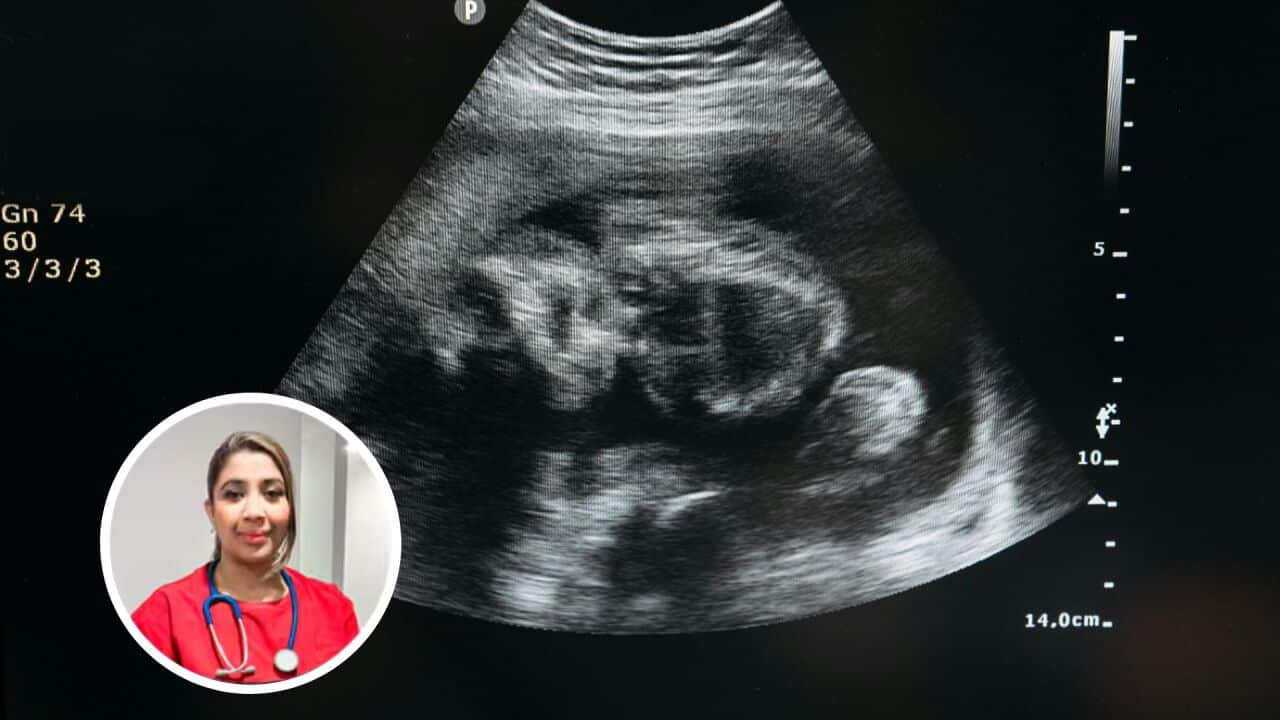

SBS Sinhala discussion with Dr. Erandi Fernando (MBBS) - Melbourne, VIC